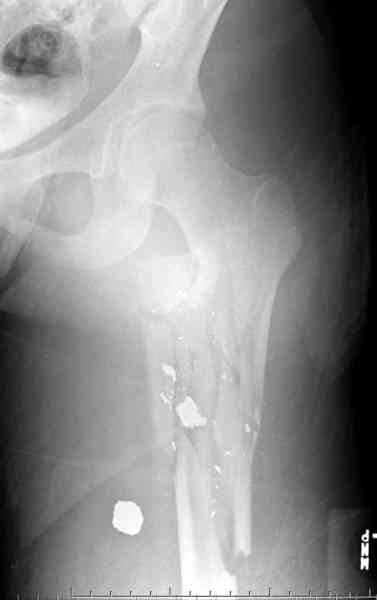

Молодой, с общим состоянием без проблем. Больной соперирован в день поступления и через два дня после операции выписан, так что не успел развиться гной.

Перелом низкоскоростным оружием, типа пистолетного, так что не стали гоняться за пулевыми фрагментами. С нервом пока подождем, иногда нерв восстанавливается если не прямое попадание в нерв, а "сотрясение" (shock wave injury).

Из всех типов фиксации взяли малоинвазивную технику мостовидной пластиной, использовали Locking проксимальную Synthes пластину.

Djoldas Kuldjanov, MD

Department of Orthopedic Surgery

St. Louis University Medical Center